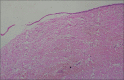

Histopathological examination is considered as gold standard procedure for arriving at a final diagnosis of various lesions of the human body. However, it is limited by a number of alterations of normal morphologic and cytological features that occur as a result of presence of artifacts. These artifacts may occur during surgical removal, fixation, tissue processing, embedding and microtomy and staining and mounting procedures. They can even lead to complete uselessness of the tissue. It is therefore essential to identify the commonly occurring artifacts during histopathological interpretations of tissue sections. This article reviews the common artifacts encountered during slide examination alongside the remedial measures which can be undertaken to differentiate between an artifact and tissue constituent.